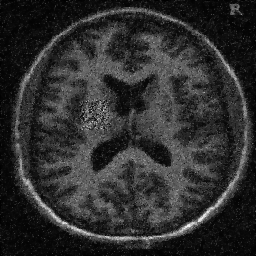

4.1. Uniform Gaussian noise

In this first experiment, we consider the denoising problem with brain scan images. The first set consists of images of pixels and Gaussian noise with zero mean and variance . The original and noisy images are shown in Figure 4.1. The domain decomposition-semismooth Newton algorithms run with the parameter values , , and . The results are shown in Figure 4.2. From the surface representation of , we can observe that is continuous and its shape is related to the one of the original image. In particular, the regularization is stronger in homogeneous regions in the image, and weaker where the image intensity undergoes variations on a smaller scale.